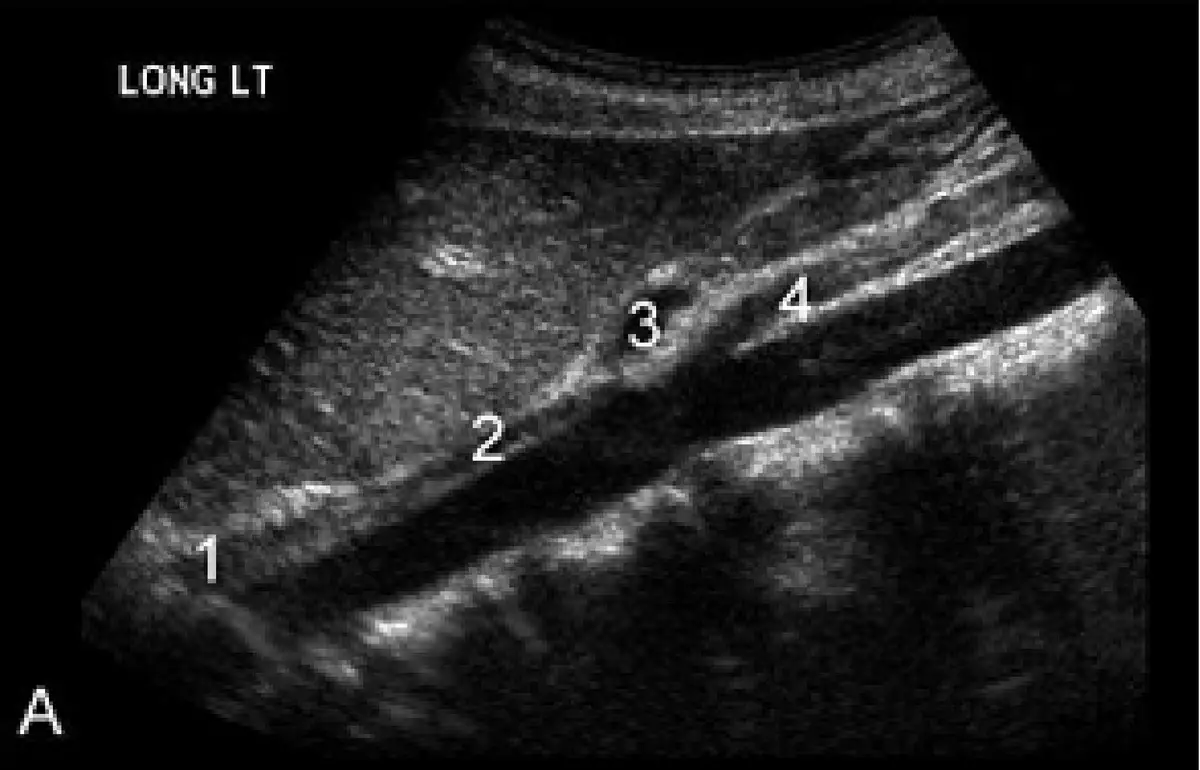

附圖為腹部縱向超音波掃描影像,編號 3為下列何者?

圖片標示「LONG LT」,為腹部左側縱向(矢狀)超音波掃描影像,可見四個編號的管狀無回音(anechoic)結構:

- 編號 1(影像左下方,最大管徑):位於後方、管徑最粗的管狀結構,為主動脈(aorta)。

- 編號 2(自主動脈前壁往右上方斜行的較大血管):從主動脈前壁分出、斜向前上方走行,為上腸繫膜動脈(SMA)。SMA 在縱向掃描中與主動脈形成典型的平行走行,並可見其夾住左腎靜脈(left renal vein)的解剖特徵。

- 編號 3(位於編號 2 分支起始處的上方小血管結構):位於主動脈前壁更靠近頭側(cranial)的短小分支,緊鄰膈肌下方,即為腹腔動脈幹(celiac trunk)。腹腔動脈幹從主動脈前壁於 T12 椎體水準分出,為腹主動脈的第一個前分支,走行極短後即分為肝總動脈(common hepatic artery)和脾動脈(splenic artery),形成「海鷗